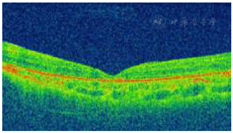

2018年11月26日:患儿左眼视网膜激光光凝术后首次回院复查,体检:右眼同前;Vos:0.04,+1.5 DS/+1.50 DC×75°→0.1,Ios:10 mmHg,左眼眼底未见明显改善,鼻下视网膜球形隆起基本同前(图4、图5),遂予左眼第一次外科手术:视网膜下液外引流联合冷凝联合玻璃体腔穿刺注药(曲安奈德、康柏西普)。